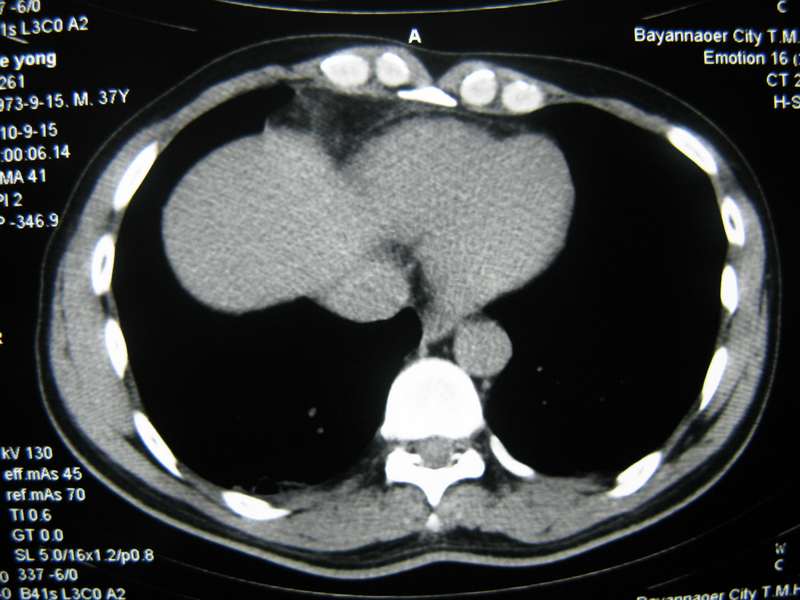

男,37岁,主述胸疼厉害,无咳嗽,无发热,血象也不高,病灶内ct值脂肪密度,右侧胸腔内少量积液,同道们考虑什么?谢谢!

脂肪垫,右下肺感染,少许积液是症状所在

纵膈脂肪堆积,右肺慢性炎症。

两肺下叶基底段纤维灶,右肺下叶基底背侧相应胸膜肥厚,右肺中叶内侧段部分不张。前中下纵隔团块状脂肪影,随访除外胸腺脂肪瘤。

纵膈脂肪堆积,右肺慢性炎症

不除外膈疝。